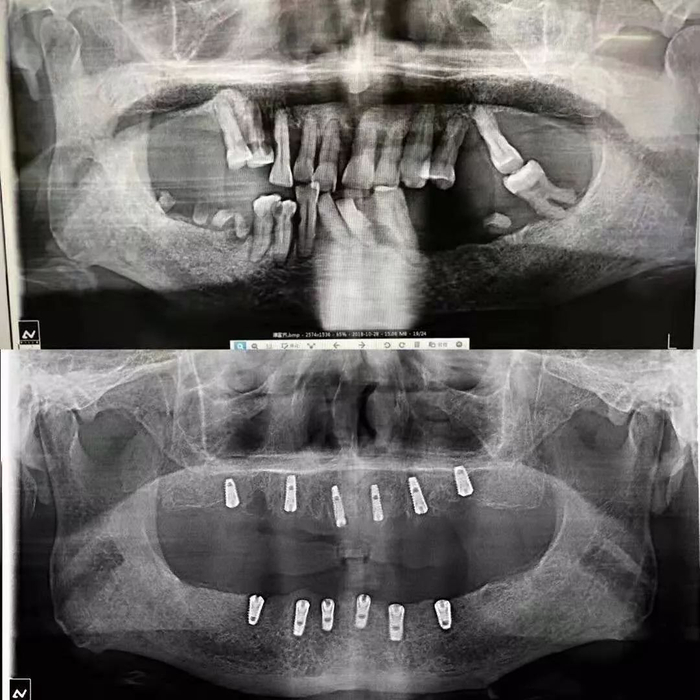

全口种植案例

△一颗牙齿都没有

△牙齿种植成功